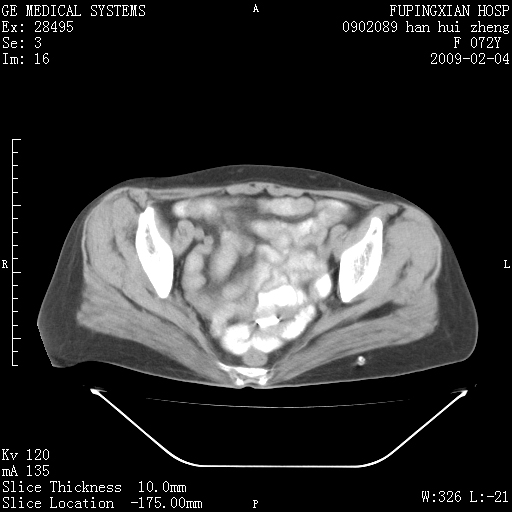

标题: CT17930:F72Y,右腹部包块5日,脐右扪及一包块,触痛。 [打印本页]

标题: CT17930:F72Y,右腹部包块5日,脐右扪及一包块,触痛。

胆囊增大,虽然内壁光滑,但囊壁不均匀性增厚,胆囊窝积液,所以首先考虑胆囊炎,但并不能排除胆囊癌的可能。诊断胆囊癌的依据是:胆囊壁呈不均匀性明显增厚,部分层面胆囊与肝脏界限不清。